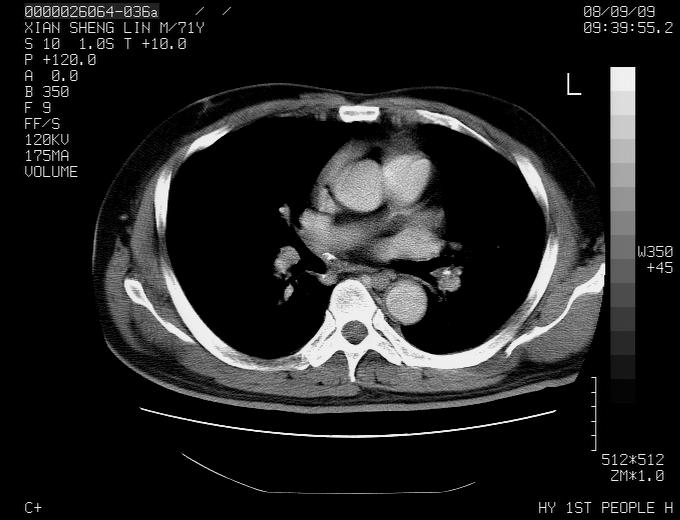

标题: CT15869:男性,71岁,因咳嗽而就诊,请讨论右上肺病变性质 [打印本页]

标题: CT15869:男性,71岁,因咳嗽而就诊,请讨论右上肺病变性质

患者,男性,71岁,因咳嗽而就诊,

典型的右肺中心性肺癌并纵隔淋巴结转移

病灶中等程度强化 还是支持肺癌诊断

考虑右肺中心性肺癌并右肺门及纵隔淋巴结转移。

1,右肺中心型ca,气管隆突旁淋巴结转移。

2,右膈明显抬高,建议肝脏扫描排除转移或原发灶。